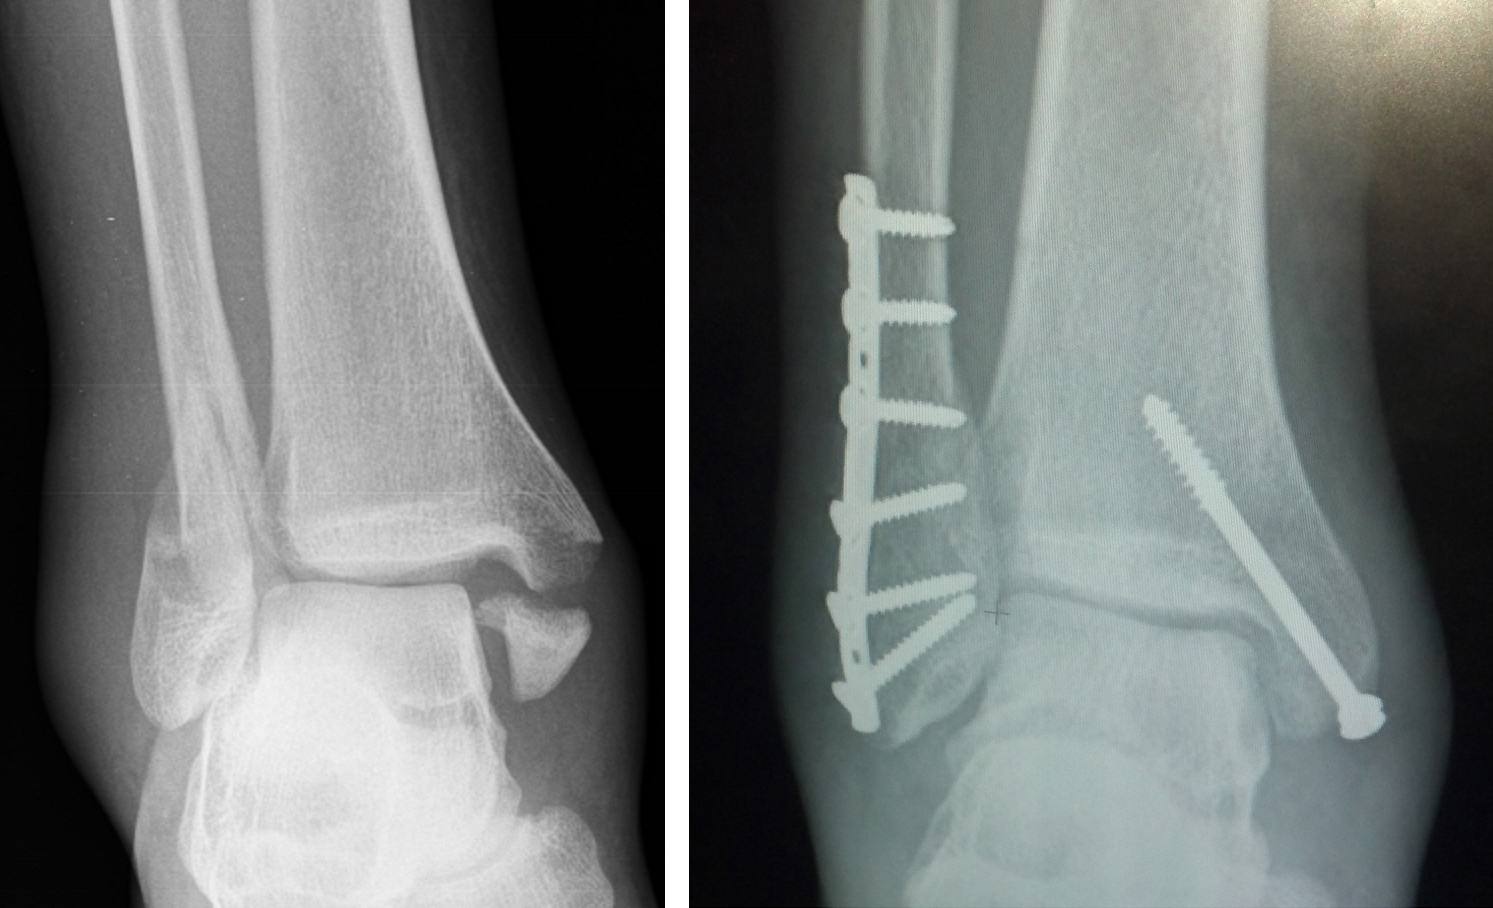

하지만 X-ray상에서 골절된 뼈가 원래 위치에서 벗어나있는 경우에는, 요즘은 대부분 빠른 일상생활로의 복귀와 추후 발생할 합병증을 최소화 하기 위해, 수술적 처치를 하게 됩니다.

2) X-ray상 골절이 확실하고, 수술을 계획하는 경우

골절 수술은 일종의 퍼즐맞추기와 같다고 할 수 있습니다. 제자리에서 떨어져나간 뼈조각을 원래 위치에 맞추어 고정을 시켜야 하는 수술입니다. 이를 위해서 수술전에는 내가 어떠한 기구를 이용하여 어느 방향으로부터 진입해서 뼈조각을 고정할 지에 대한 계획을 하게되는데요, 이를 CT 검사를 통해 도움을 받을 수 있습니다. X-ray로도 할 수 있지만은, 앞서 말씀드린 것처럼 그림자만으로 계획을 했을 경우에 만약에라도 발생할 불상사를 예방하기 위해서라도, 좋은 수술 결과를 바란다면 CT검사를 하는 것이 좋습니다.